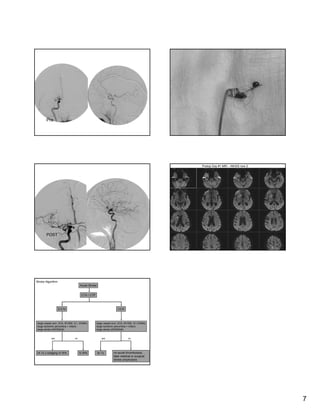

Stroke is a major cause of death and disability in the United States and worldwide. While intravenous tissue plasminogen activator (tPA) can effectively treat acute ischemic stroke, few patients receive it due to its narrow time window and contraindications. Endovascular therapies including mechanical clot retrieval may extend the treatment window and benefit more patients, especially those with severe or large vessel strokes. New devices and techniques continue to improve revascularization rates and outcomes for acute stroke.